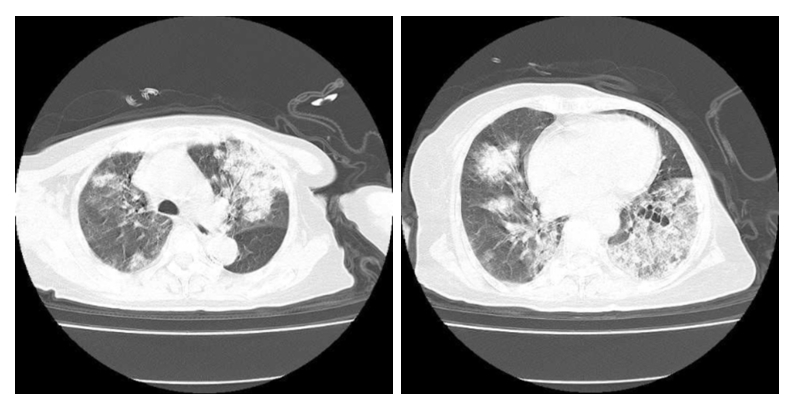

入院查体:体温37.8℃,心率92次/min,呼吸30次/min,血压108/65 mmHg(1 mmHg=0.133 kPa)。神志清楚,查体可配合,皮肤黏膜未见异常,浅表淋巴结未及肿大。口唇轻度紫绀,颈静脉充盈,双肺呼吸音粗, 双肺可闻及湿啰音。心律不齐,主动脉瓣区及三尖瓣膜区可闻及3/6级收缩期杂音。腹软、无压痛及反跳痛。双下肢轻度凹陷性水肿。辅助检查:血常规:白细胞(WBC)9.29×109/L、中性粒细胞计数(NEUT)8.14×109/L、淋巴细胞绝对值:0.78×109/L、红细胞计数(RBC)2.90×1012/L、血红蛋白(HGB)86.00 g/L、血小板计数(PLT)134.00×109/L。C反应蛋白(CRP)114.11 mg/L,白介素6(IL-6)45.30 pg/mL,降钙素原(PCT)0.54 ng/mL。总胆红素(TBIL):27.65 μmol/L、白蛋白(ALB)29.00 g/L、丙氨酸氨基转移酶(ALT)30.06 U/L、天门冬氨酸氨基转移酶(AST)41.30 U/L。肌酐(Scr)98.20 μmol/L、尿酸(UA)453.60μmol/L、尿素氮(BUN)13.38 mmol/L。钾(K+)3.01 mmol/L、氯(Cl-):109.09 mmol/L、钙(Ca2+)1.99 mmol/L。高敏肌钙蛋白Ⅰ(cTnI)78.30 pg/mL、肌红蛋白(Mb)88.10 ng/mL、B型尿钠肽(BNP)449.80 pg/mL。血沉(ESR)104.0 mm/h,类风湿因子(RF)37.67 IU/mL,补体C3:0.70 g/L、补体C4:0.17 g/L。尿液分析:隐血+3、白细胞+1、尿蛋白+3。凝血功能:D-二聚体:0.78 μg/mL、余正常。血气分析:pH 7.376、PaCO2 31.3 mmHg、PaO2 65.4 mmHg(鼻导管吸氧,FiO2: 30%)、BE-4.2 mmol/L、HCO3- 20.3 mmol/L、Lac 0.9 mmol/L。1, 3-β-D葡聚糖检测阴性,结核抗体、TORCH十项、呼吸道九项、EB病毒均为阴性。心电图示:窦性心律;室性早搏伴有长QTc间期。心脏彩超:三尖瓣少量反流。左室舒张功能减低。胸部CT:双肺感染,双肺见多发磨玻璃样及片状高密度影,部分实变(图 1)。入院初步诊断:①呼吸衰竭;②重症肺炎;③咯血待查;④轻度系统性红斑狼疮;⑤左心功能不全NYHA分级Ⅲ级;⑥心律失常室早;⑦电解质代谢紊乱低钾、低钙血症;⑧左乳腺癌术后;⑨左侧髋关节置换术后。予美罗培南(1.0 g, ivgtt, q8h)+左氧氟沙星氯化钠注射液(0.5 g, ivgtt, qd)抗感染治疗,患者狼疮性肺炎不能排除,予甲泼尼龙(40 mg,静脉注射,qd)治疗,白眉蛇毒血凝酶(1ku, iv, q12h)止血、呋塞米(20 mg, po, qd)+螺内酯(20 mg, po, qd)利尿。盐酸沙丁胺醇+布地奈德混悬液+异丙托溴胺雾化治疗,奥美拉唑护胃,莫沙比利促进胃肠动力以及维持内环境稳定等治疗。

| 图 1 患者2022-03-22胸部CT检查影像 |